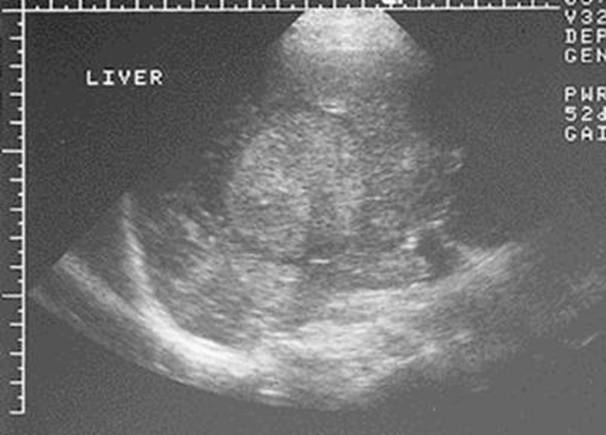

Дані інструментальних

методів

дослідження

(УЗД нирок та

сечових

шляхів, екскреторна

урографія, сканографія, комп’ютерна

томографія)

допомагають

встановленню

діагнозу.

При

рентгенологічному, ультразвуковому

дослідженні

нирок, комп’ютерній

томографії

знаходять

розширення і

деформацію

ниркових

мисок

різного

ступеня

вираженості, асиметрію,

зморщення

нирок.